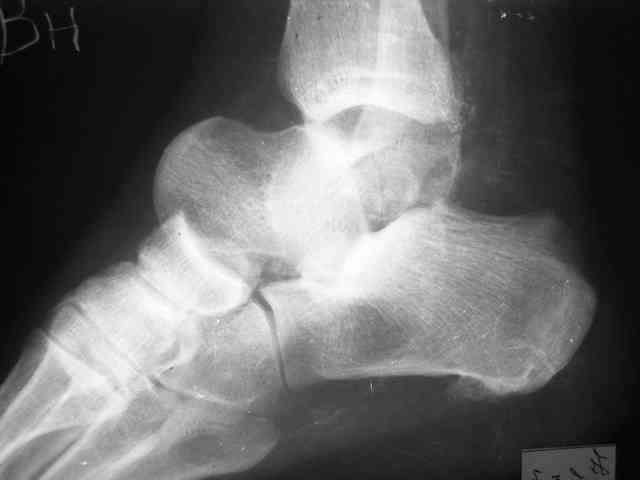

Уважаемый Александр! Как обещал представляю Р-граммы и операционные фото.

Опять надоедаю с вопросами:

Ваши (лично ваши) рекомендации - астрагалэктомия-аппаратный пяточно-большеберцовый артродез с одновременным удлинением голени - правильно?

Можно убрать таранную кость, и поместить в образовавшуюся полость либо бусы из цемента с антибиотиками, либо вылепленный прямо по форме тарана спейсер. Целесообразность этого будет определяться распространенностью гнойного процесса. Может быть, будет достаточно только удаления тарана.

Вместе с аваскулярным куском кости устранится субстрат. Надо опасаться не мягких тканей, а плохо кровоснабжаемых. Если после удаления тарана добиться контакта хорошо васкуляризованных пятки и больщшеберцовой, мягкие ткани не давить, чтобы некроза раны не было, то все должно зажить.

Стабильность дает возможность расти сосудам. При хорошем кровоснабжении смежных фрагментов это все, что надо. А здесь есть большой секвестр. Разумно ли ждать, пока он васкуляризуется? Очевидно, без некрэктомии проблему не решить.